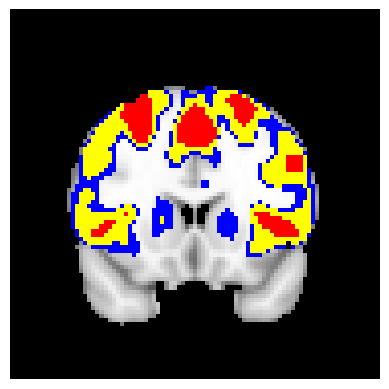

The confidence regions are constructed on fMRI scans from 77 subjects as a real data application of the proposed methods after applying additional smoothing with Gaussian kernel with FWHM to match the results shown in Bowring (2019) [BOWRING2019116187]. Confidence regions using 1) the joint method with , 2) the separate method with BH adjustment for upper and lower side each with , 3) the separate method with BH adjustment for upper side and two-stage adaptive procedure for lower with , and 4) SSS () were compared with threshold level 1.0%, 1.5%, and 2.0% Blood Oxygenation Level Dependent (BOLD) change. Joint control confidence regions are produced with instead of 0.05 for the reasons mentioned in chapter 3.

For all slices, FDR controlling methods show tighter inference of both upper and lower CR compared to the SSS method. SSS shows smaller upper CR and larger lower CR which suggests more conservative inference compared to FDR controlling testing based methodologies. This is due to the fact that by controlling for FDR, the method allows for more false discoveries in exchange for more discoveries in general. Despite having higher level at , joint control confidence regions still show comparable results to other methods even with higher significance level. Naturally, as the threshold goes up, the area enclosed between the upper and lower confidence regions decreases.

Confidence regions with separate controls of FDR for lower and upper are presented in two forms for comparison: one with BH procedure for the lower confidence region, and the other one with the two-stage adaptive procedure for the lower confidence region. The upper confidence region remains the same as both methods uses BH procedure for the upper set FDR control. Lower confidence regions with adaptive method are smaller than lower sets with BH procedure which is to be expected as the two-stage adaptive procedure is less conservative when more voxels are thought to be rejected. In the context of negative one-sided testing, this is equivalent to when there are less number of voxels above than below .